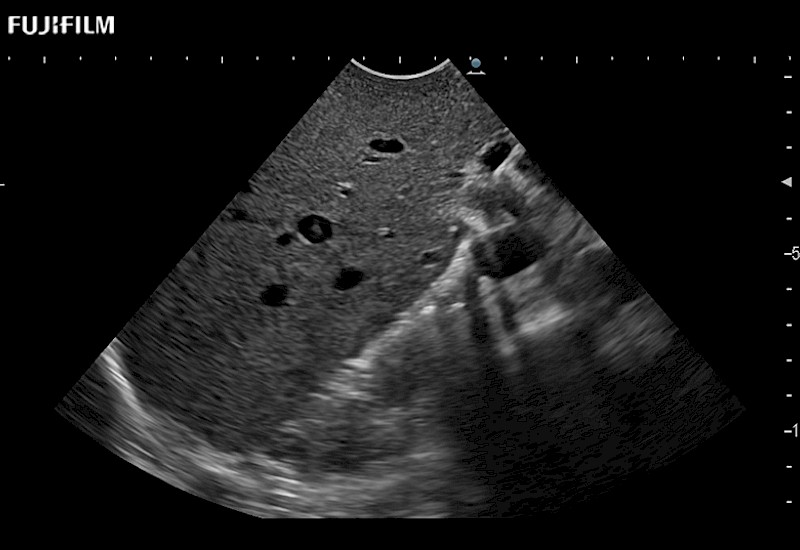

Extraordinary high-resolution digital imaging

for use during open and laparoscopic procedures: Tumor localization & staging, Ablation, Resection, Biopsy, Transplant, Abdominal exploration, Robotic surgery

- Instant feedback on tumor margin delineation

- Valuable information to guide tumor resections

- Instant feedback on tumor margin delineation

- Instant feedback on tumor margin delineation

- Instant feedback on tumor margin delineation

- Instant feedback on tumor margin delineation

- Instant feedback on tumor margin delineation

- Valuable information to guide tumor resections

- Instant feedback on tumor margin delineation

- Valuable information to guide tumor resections

- Instant feedback on tumor margin delineation

- Valuable information to guide tumor resections

- Instant feedback on tumor margin delineation

- Valuable information to guide tumor resections

- Instant feedback on tumor margin delineation

The ARIETTA 750 incorporates all of the proven technologies and functions that medical professionals have come to expect from Fujifilm Healthcare.

ARIETTA 750 is the definitive diagnostic ultrasound solution for any clinical setting - Private Office, Imaging Center, or Hospital. The ARIETTA platform provides the ultimate in clinical performance with its state-of-the-art features and large user-friendly display.

The ARIETTA 650 DI combines trusted Fujifilm Healthcare technologies and features tailored for surgical oncology.

Designed to meet the demands of surgeons, the ARIETTA 650 DI offers precise guidance. Its advanced capabilities and large, intuitive display offer accurate and efficient care in operating rooms and specialized surgical settings.